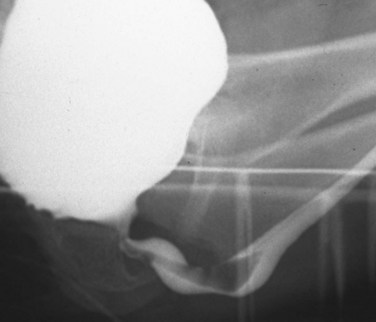

Figure 126–2 A, Voiding cystourethrogram demonstrates a typical type I posterior urethral valve with a dilated posterior urethra, elevated bladder neck, and valve leaflets obstructing the flow of contrast material from the bladder. B, This cystoscopic image from the distal urethra shows the valve leaflets forced into the lumen with the bladder full, illustrating their obstructive effect.

Young’s type I valves make up 95% of all posterior urethral obstructions (Fig. 126–2).